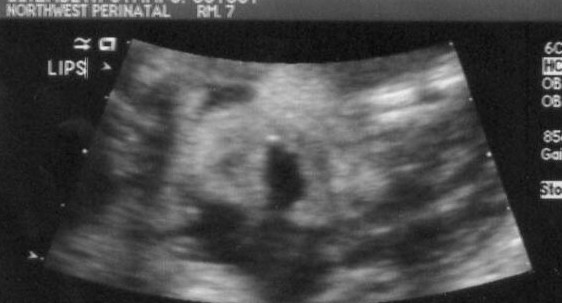

Here is one of his lower face (sideways). The mouth is open and the nostrils of his nose are clearly visible. How fun is that?